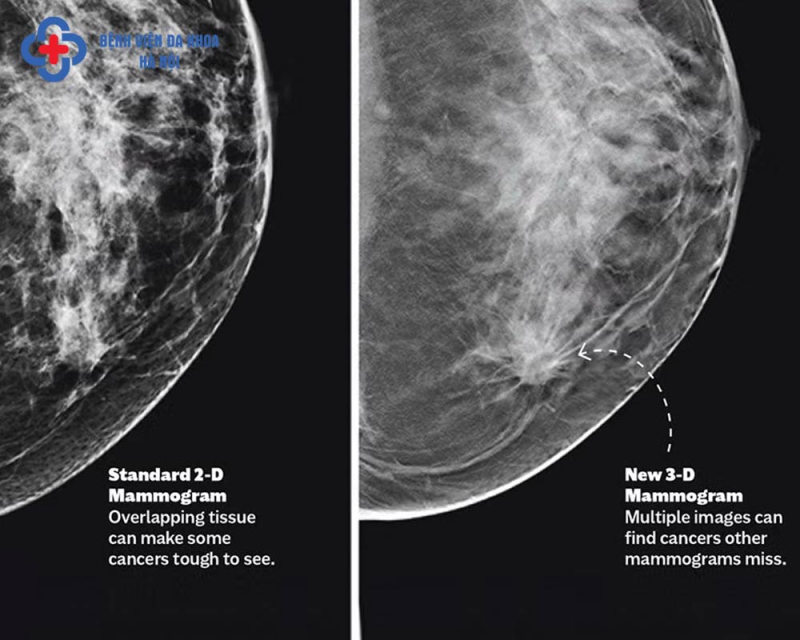

Cũng theo Ths. BS CKII Đỗ Đức Linh, thực tế khám lâm sàng và siêu âm rất khó phát hiện được các vi vôi hoá - là những đám canxi lắng đọng, rất đa dạng về hình thái, kích thước, số lượng và sự phân bố trong tuyến vú. Trong một số trường hợp, vi vôi hóa là dấu hiệu ung thư ở giai đoạn sớm và nhũ ảnh là phương tiện có ưu thế tuyệt đối so với siêu âm và MRI trong việc phát hiện, đánh giá, phân loại những tổn thương dạng vi vôi để có hướng chẩn đoán, xử trí phù hợp. Ngoài ra nhũ ảnh còn giúp hướng dẫn cho sinh thiết nhằm xác định bản chất tổn thương.

Lợi ích vượt trội của nhũ ảnh 3D và khuyến nghị tầm soát định kỳ

Ths. BS CKII Đỗ Đức Linh cho biết: "Phụ nữ trên 40 tuổi tầm soát ung thư vú bằng chụp nhũ ảnh hàng năm giảm 40% tỷ lệ tử vong vì ung thư vú so với nhóm không tầm soát. Chụp nhũ ảnh giúp phát hiện ung thư vú từ rất sớm, ngay khi chưa có triệu chứng lâm sàng".

Với đầy đủ các danh mục thiết yếu trong tầm soát bệnh tuyến vú, đa dạng gói khám, cùng trang thiết bị, máy móc hiện đại nhập khẩu chính hãng từ Âu – Mỹ (như hệ thống chụp nhũ ảnh 3D tiên tiến nhất hiện nay), Bệnh viện Đa khoa Hà Nội tự hào là địa chỉ uy tín. Đội ngũ chuyên gia đầu ngành, bác sĩ giàu kinh nghiệm trong chẩn đoán và điều trị bệnh tuyến vú, cam kết mang lại kết quả chẩn đoán nhanh chóng, chính xác. Chi phí hợp lý, không gian thăm khám đạt tiêu chuẩn quốc tế và dịch vụ tận tâm, chu đáo như người nhà là những yếu tố giúp Bệnh viện Đa khoa Hà Nội trở thành lựa chọn hàng đầu cho sức khỏe của người dân.